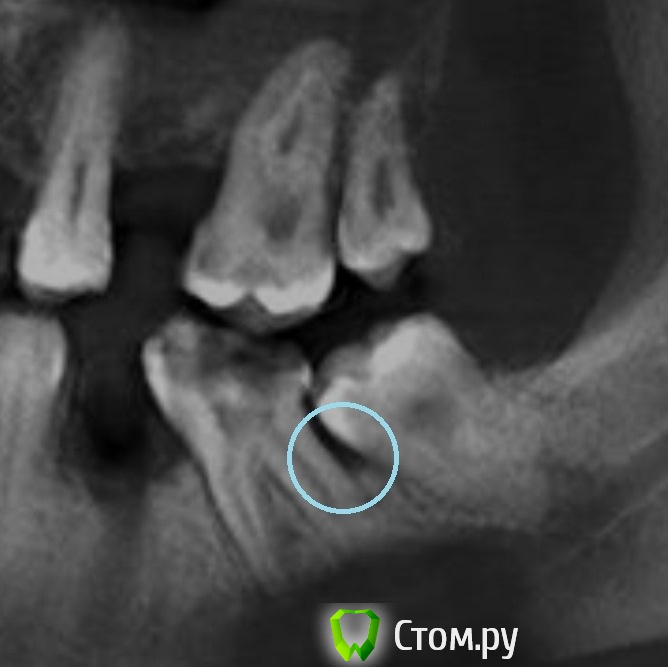

sergey765 Опубликовано 13 июня, 2014 Автор Поделиться Опубликовано 13 июня, 2014 может у меня там вообще какой-нибудь рак... и крышку гроба уже пора заказывать... что допустим во это вот за фигня Ссылка на комментарий

dr-krasnov Опубликовано 13 июня, 2014 Поделиться Опубликовано 13 июня, 2014 (изменено) Еще поживете) Вот распечатайте, покажите врачу. http://s018.radikal.ru/i515/1406/73/c016294351c5.jpg Изменено 13 июня, 2014 пользователем dr-krasnov Ссылка на комментарий

sergey765 Опубликовано 13 июня, 2014 Автор Поделиться Опубликовано 13 июня, 2014 Еще поживете) Вот распечатайте, покажите врачу. http://s018.radikal.ru/i515/1406/73/c016294351c5.jpg)))) ну это хорошо что поживу... та особо страшного ничего нет? может вообще тогда ещё подождать пока лунка заживет недельки 2 и если все будет нормально тогда пойти с эти снимком к стоматологу который лечит... и залечить этот больной зуб? Ссылка на комментарий